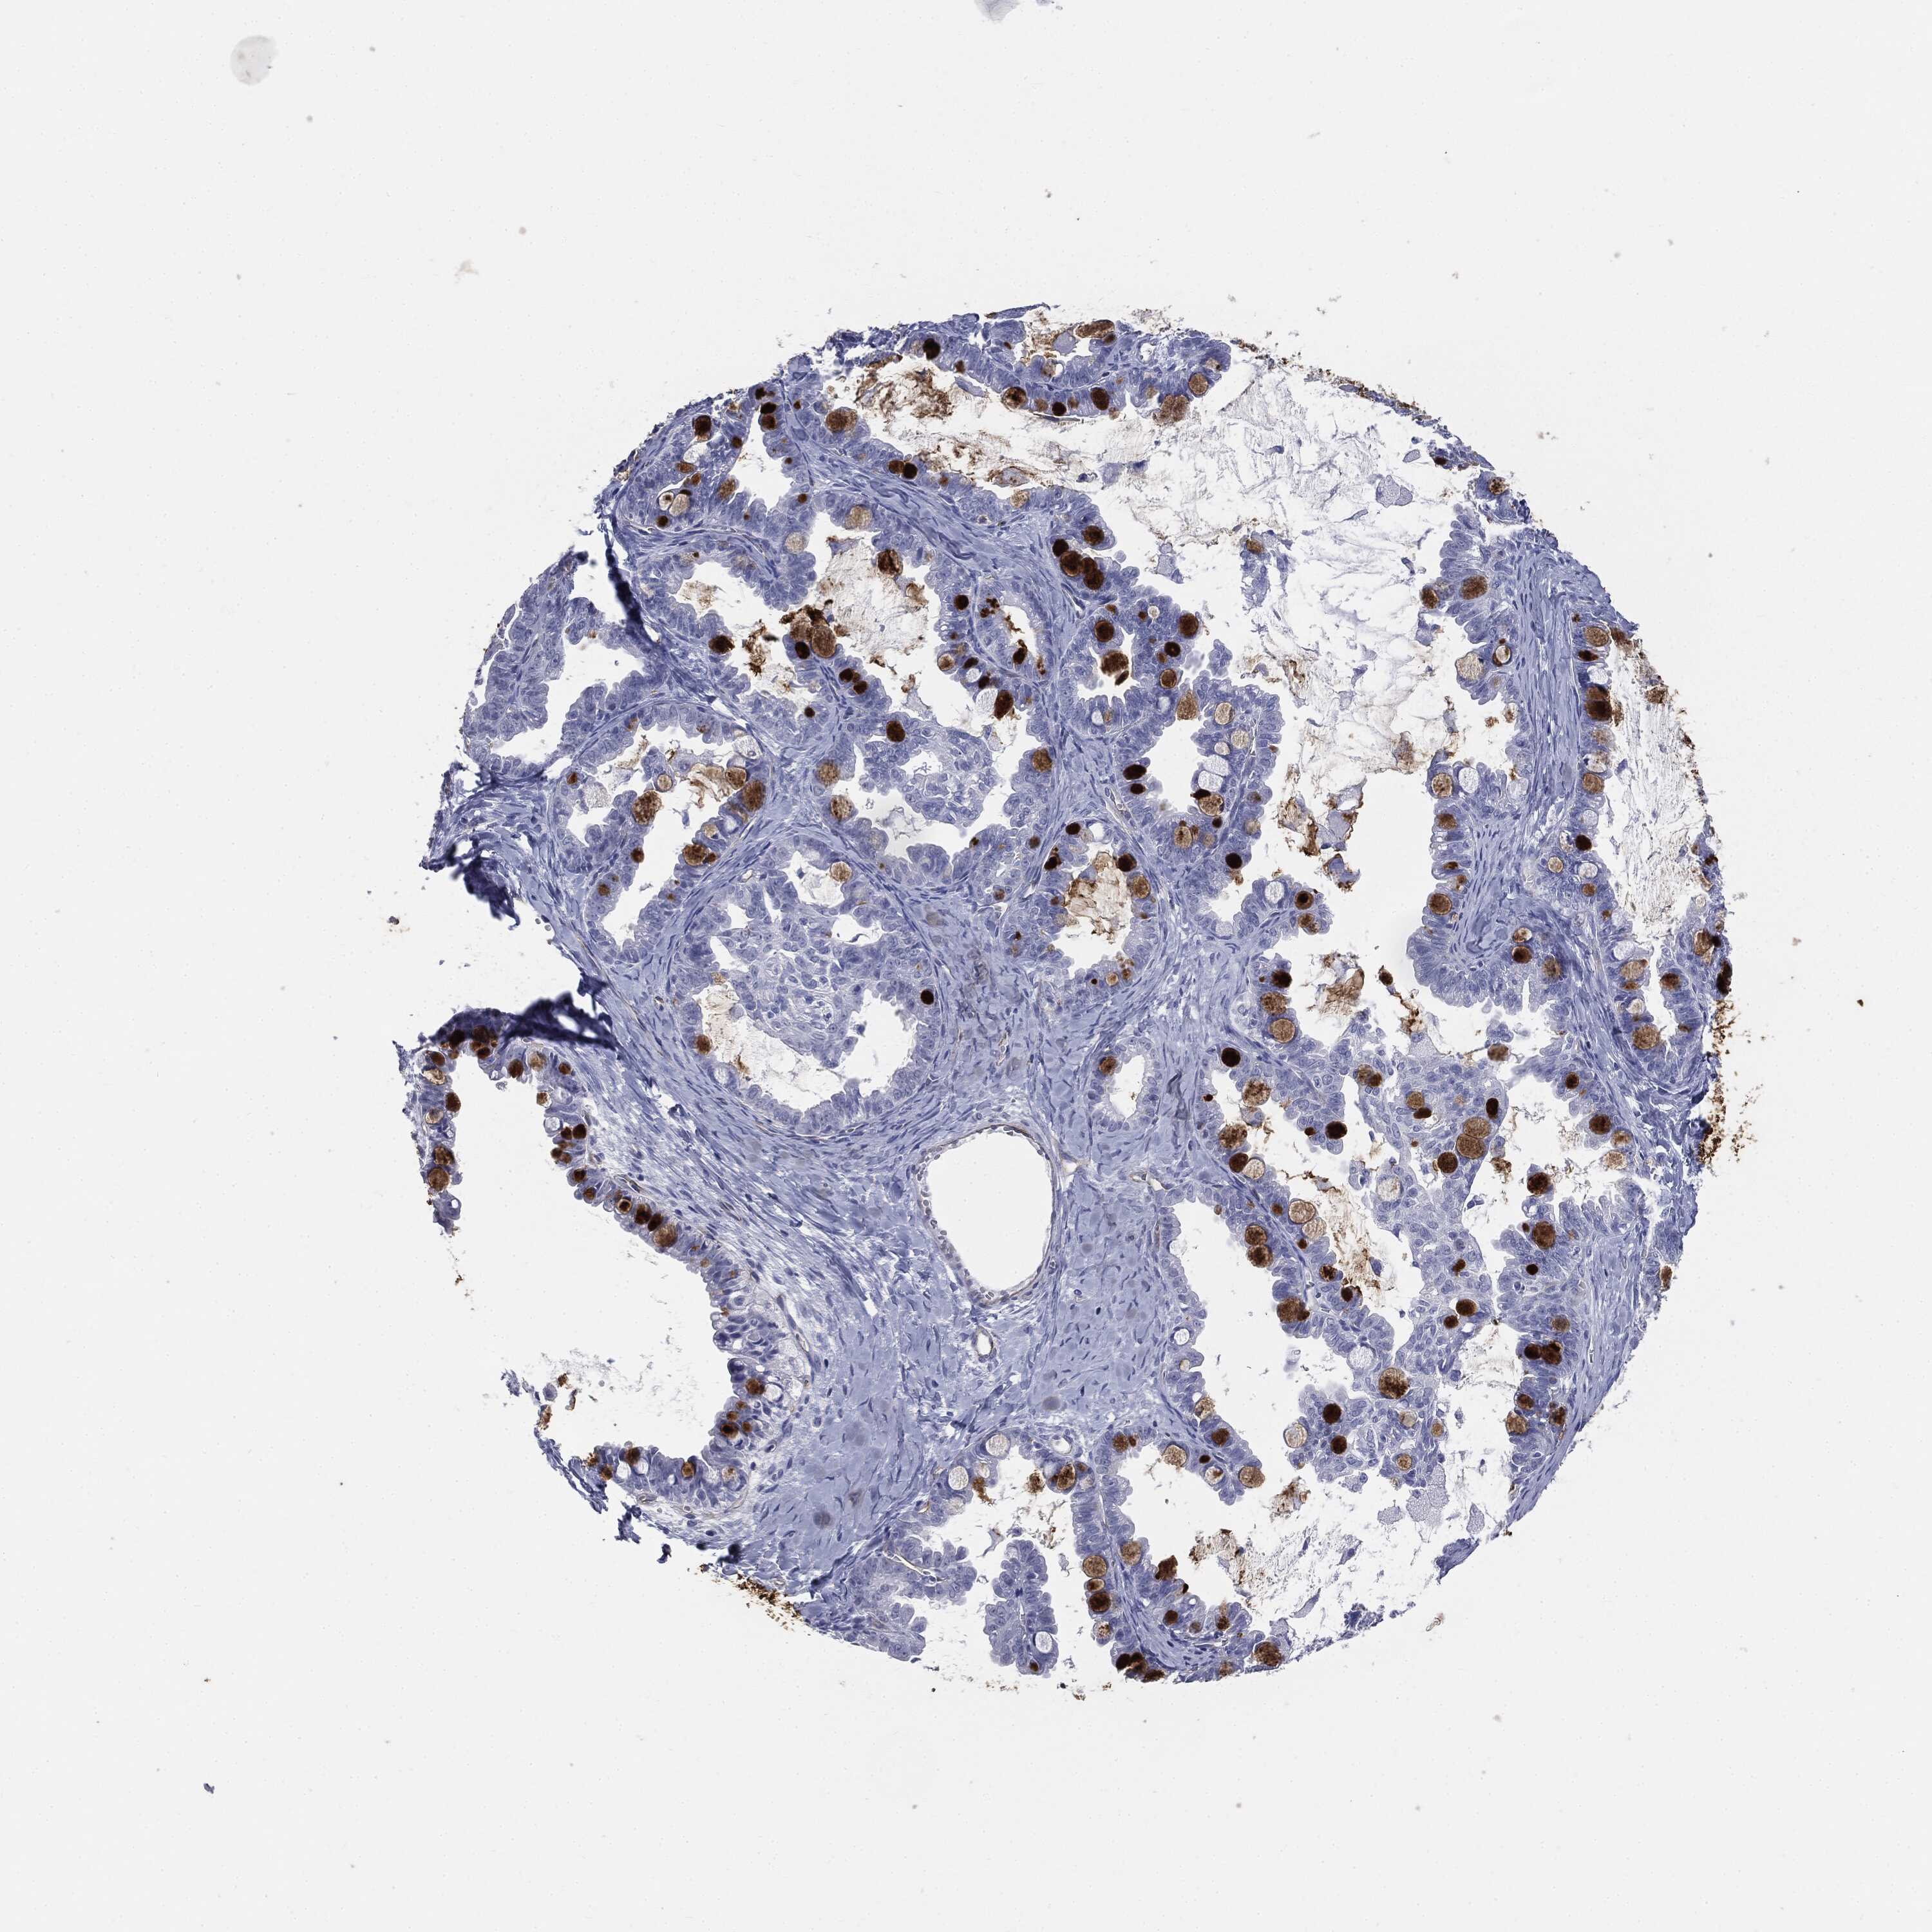

OVARIAN CANCER - Protein expressioni

A mouse-over function shows sample information and annotation data. Click on an image to view it in a full screen mode. Samples can be filtered based on level of antibody staining by selecting one or several of the following categories: high, medium, low and not detected. The assay and annotation is described here.

Note that samples used for immunohistochemistry by the Human Protein Atlas do not correspond to samples in the TCGA dataset.

Antibody stainingi

Antibody staining in the annotated cell types in the current human tissue is reported as not detected, low, medium, or high, based on conventional immunohistochemistry profiling in selected tissues. This score is based on the combination of the staining intensity and fraction of stained cells.

Each image is clickable and will lead to virtual microscopy that enables deeper exploration of all samples and also displays staining intensity scores, fraction scores and subcellular localization as well as patient and tissue information for each sample.

HPA040615

Cystadenocarcinoma, serous, NOS

Carcinoma, endometroid

Cystadenocarcinoma, mucinous, NOS

Carcinoma, NOS